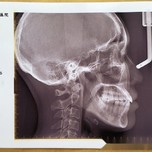

一直以来总觉得下唇略向右偏斜,小时候不明所以,老妈以为我是故意的,还总揍我,谁想到是反颌在作祟呢这次经过北京薇琳齿科面部核磁、X光片等检查,还有专业正畸医生的诊断,就是有一颗牙齿位置略偏,没有长在合适的

💡什么是骨性地包天?骨性地包天(下颌前突)属于颌面发育异常问题,主要表现为下颌骨过度前伸,导致“月亮脸”或“鞋拔子脸”面型,属于骨性错颌畸形(牙性地包天可通过正畸改善,而骨性需手shu介入)。 ⚠【地包天常见成因】 1⃣ 遗传因素:家族中有下颌前突或颌骨发育异常史 2⃣ 不良习惯:长期口呼吸/咬下唇/吮手指(影响颌骨发育) 3⃣ 创伤或疾病:儿童期颌骨外伤、垂体功能亢进等🔍【骨性地包天的5大面型特